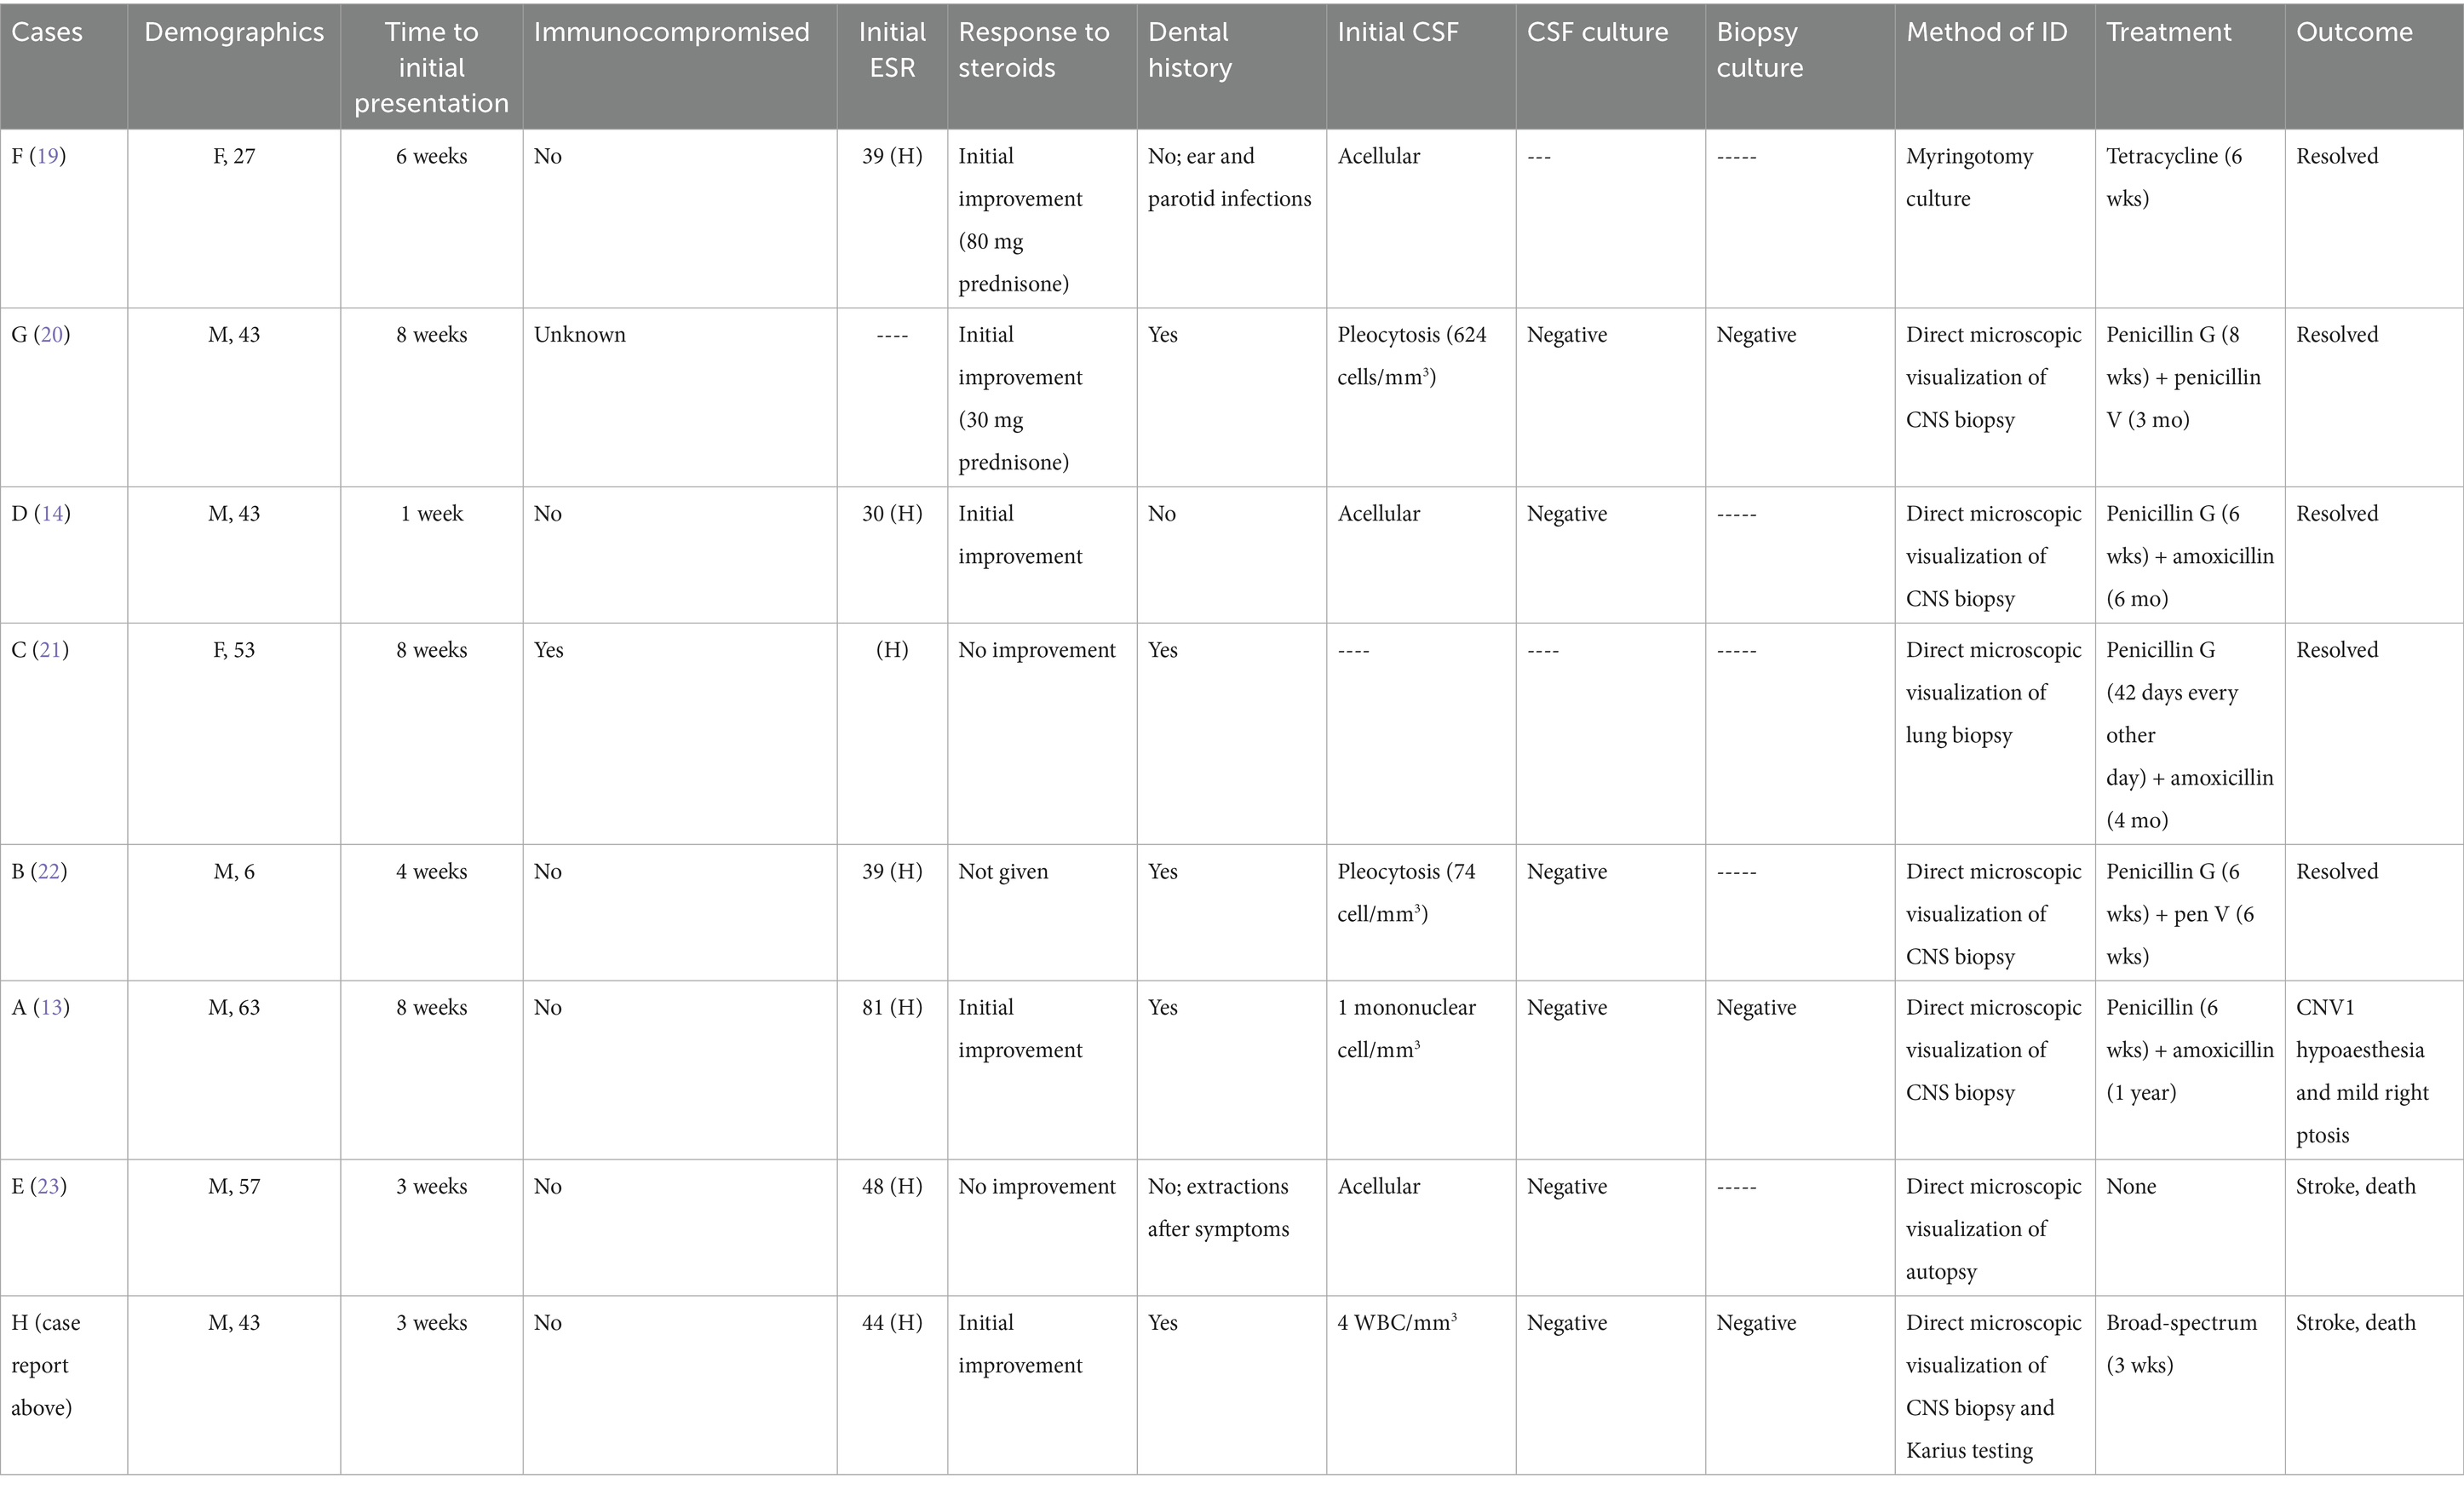

This systematic review identified seven additional cases of CNS actinomycosis that mimicked THS (Table 2). The eight identified cases showed a male predominance, with 75% of patients being male. Ages ranged from 6 to 63 years, with a median age of 43. These cases did not seem to be specific to a particular ethnic population and were reported in Italy, Spain, the United Kingdom, Japan, Australia, and the United States.

Each patient presented with eye pain and diplopia, with or without headaches, aligning with the THS diagnostic triad. The average time to presentation was 5.1 weeks, ranging from 1 to 8 weeks. A total of seven of the eight cases were localized to the cervicofacial region. Furthermore, one patient had disseminated actinomycosis and was on immunosuppressive medications, while five patients had dental infections or extractions prior to symptom onset, and one had extractions after symptom onset. Moreover, one case was associated with otitis media, while five cases had a fever on presentation or during hospitalization. Pleocytosis was noted in three of the cases, each occurring weeks to months after initial presentation. CSF cultures were obtained in 75% of the cases, all of which were negative. In addition, three cases reported culturing of biopsied tissue, each returning negative. In seven of the eight cases, the diagnosis was made by histopathologic examination, consistent with Actinomyces, through direct visualization of branching filaments, with or without the presence of sulfur granules. The biopsy sources were the cavernous sinus (n = 6) and the lung (n = 1). The only case to successfully culture Actinomyces obtained the cultured specimen via myringotomy. No cases reported isolation of Actinomyces from blood cultures.

Treatment/outcome

In total, five cases were treated with IV penicillin for a duration of 6–8 weeks, followed by oral penicillin/amoxicillin for 6–52 weeks. In addition, one case of disseminated actinomycosis received IV penicillin every other day for 42 days, followed by 16 weeks of amoxicillin, while one case was treated with 6 weeks of tetracycline. Another case received broad-spectrum antibiotics prior to expiration. Furthermore, five cases made a full recovery, while one reported CNV1 hypoesthesia and mild right ptosis. The patients in the remaining two cases passed away. Each of these cases was complicated by vasculitis, multiple acute infarcts, and coma. The autopsies showed similar abscesses in the cavernous sinus with purulent material. Of additional importance, 62.5% of the cases saw initial symptom improvement upon starting steroids. This is important because it can create a false sense of security regarding the accuracy of the diagnosis.